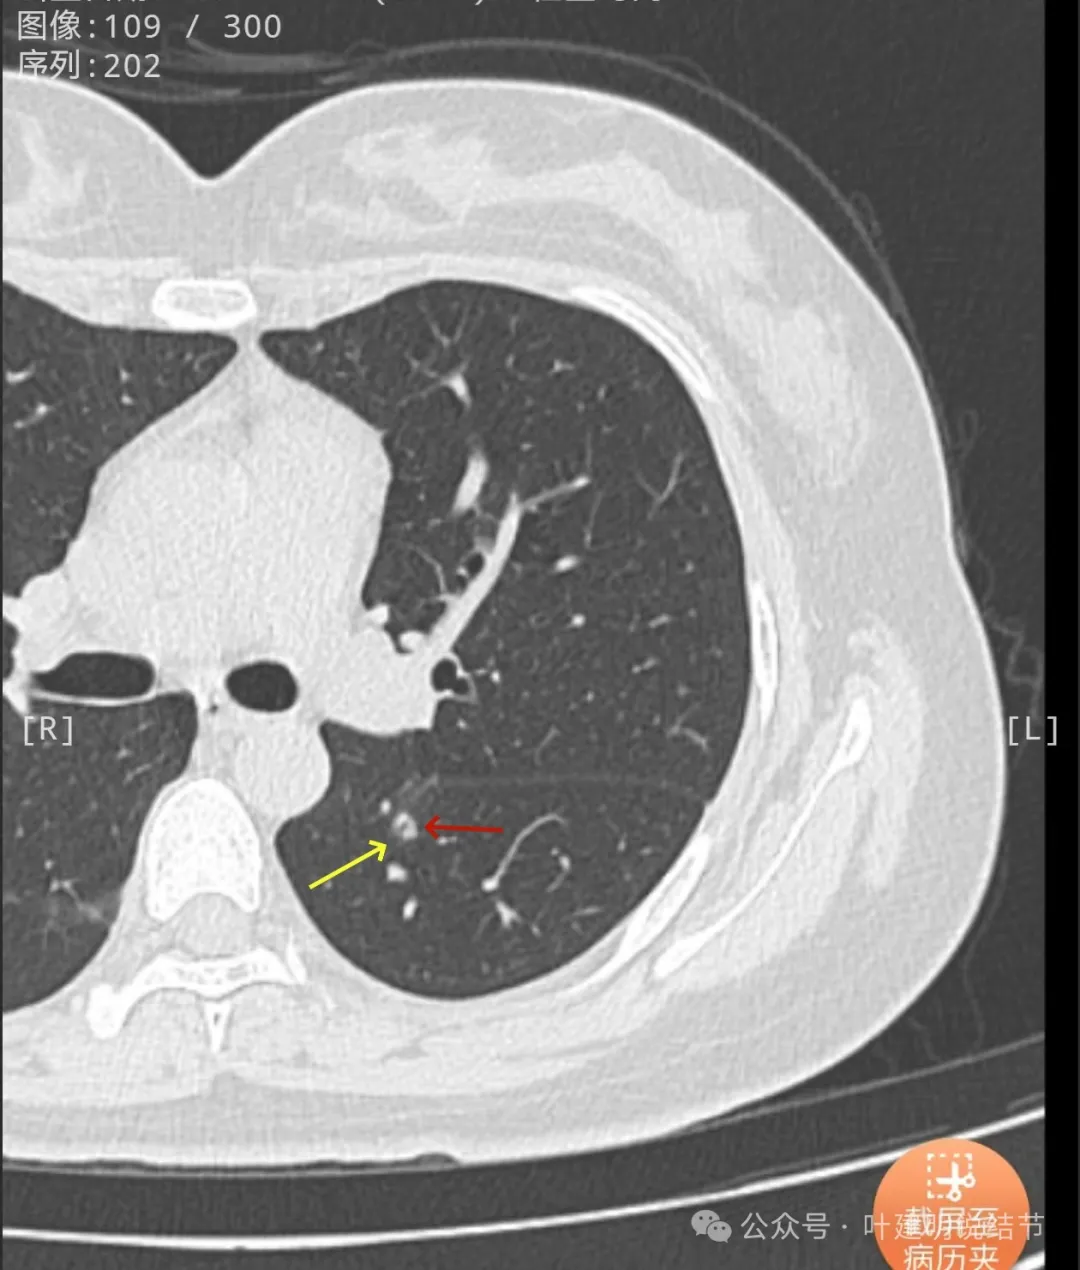

边缘区密度较淡。

冠状位实性位小空泡征的样子,与叶间裂之间有小条状相连,整体轮廓较清,空泡壁厚薄不均。

矢状位沿着叶间裂略显长条状,靠叶间裂侧密度较高,边上的低密度管道状像细支气管,横断面的上小空泡是扩张的细支气管吗?矢状位上看收缩力不明显。